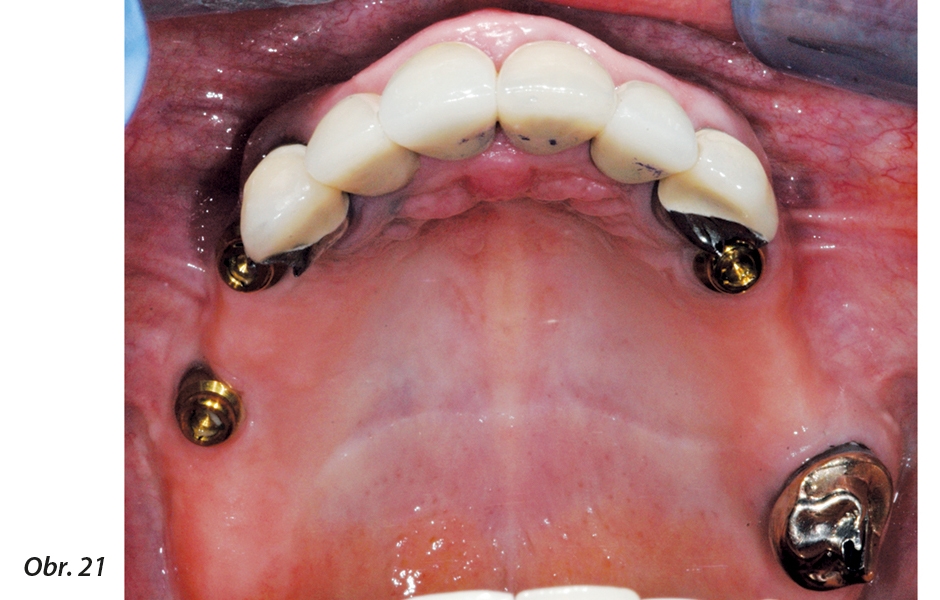

Bylo odsouhlaseno umístění implantátu na strategické pozici s ohledem na případnou ztrátu horních a dolních pilířů ČSN a současně úprava dlouhodobé konfigurace pilířů pro ČSN. Dále bylo také schváleno umístění dalšího implantátu v oblasti horního levého moláru za účelem změny konfigurace ČSN na III. třídu.

Situaci při kontrole 5 let od zavedení implantátů můžete vidět na obr. 20 a 21.

Implantát strategicky umístěný tak, aby nahrazoval chybějící pilíř pro ČSN v místě horního špičáku a posunul celkovou konfiguraci pilířů ČSN na situaci III. třídy